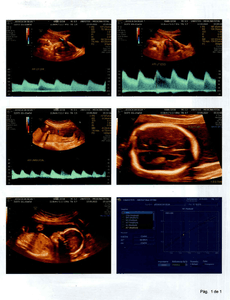

Olá amigos e amigas, eu Laidson Saturnino Souza Santos, descobri que minha filha, com idade gestacional de 21 semanas e 6 dias, foi diagnosticada com MIELOMELINGOCELE SACRAL, ESPINHA BÍFIDA OU ESPINHA ABERTA, no dia 13/09/2022, por meio de uma ultrassonografia morfológica. Ela possui uma MALFORMAÇÃO NA COLUNA. Em decorrência disto provavelmente nascerá com ANOMALIAS ESTRUTURAIS, DOENÇAS GÊNICAS, RETARDO MENTAL, CROMOSSOMOPATIAS (SINDROME DE DOWN), entre outros problemas. A única forma de tentar reverter esse problema seria uma cirurgia intrauterina, ou seja, os médicos farão uma cesárea, irão abrir o útero da mãe, chegar até meu filho, onde irão fechar a sua coluna, q está aberta. Feito isto suas chances de nascer perfeito São grandes, claro que os médicos não descartam a hipótese de haver sequelas, mas acreditamos na cura total. Se a mãe não se submeter a esse procedimento, assim q ela nascer irá pra cirurgia para fechar a coluna, mas já será tarde demais e consequentemente ficará sem andar entre outras complicações e por fim será uma menina especial pro resto da vida. Estamos aqui correndo contra o tempo, pois o prazo será até a 26ª semana, ou seja, temos 4 semanas para organizar tudo, e levantar o dinheiro. Não sabemos ao exato o quanto custa essa cirurgia, mas passa de $ 20,000 DÓLARES, aqui no Brasil. Onde moramos, Bahia, este procedimento não é realizado, só em São Paulo ou Rio de Janeiro. Então abandonaremos tudo aqui, família, amigos, ...  para tentar dar um futuro melhor para a LIZ. Estamos tentando os órgãos públicos para obtermos a cirurgia através do SUS (Sistema Único de Saúde). Mas é difícil e não temos como esperar. Então criamos uma conta para levantarmos a quantia suficiente e assim poder realizá-la. Peço que quem tiver interesse em ajudar repasse esta mensagem aos seus amigos, para juntos salvarmos a vida da minha menina.